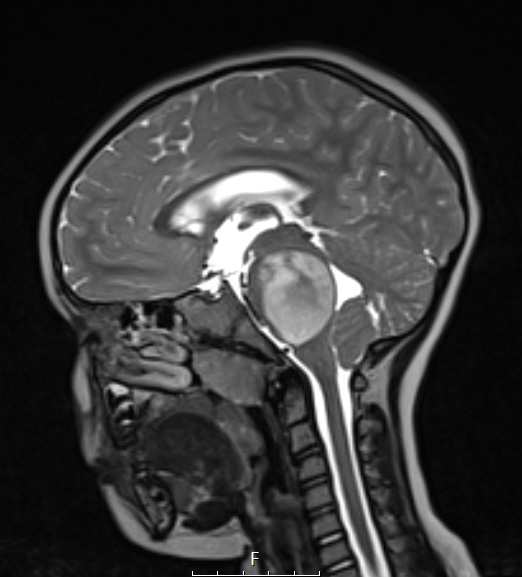

16A3,4 T2-weighted scans with (16A3) and without (16A4) contrast show a hyperintense mass.